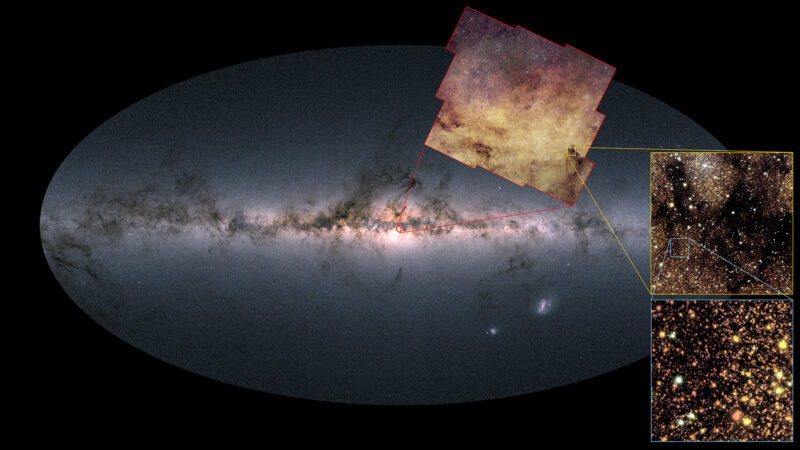

Использование компьютерной томографии для неразрушающего изучения мумии, сохранившейся в вечной мерзлоте, позволило исследователям не только «диагностировать травму, но и реконструировать результаты сложного хирургического вмешательства, выполненного в древние времена», — говорится в заявлении Владимира Каныгина, заведующего лабораторией ядерной и инновационной медицины Новосибирского государственного университета в России, «превратив единичную находку в подробное свидетельство высокого уровня медицинских знаний пазырыкской культуры».

«Этот мумифицированный участок кожи на черепе погребенной женщины делал антропологическое исследование невозможным, но нам хотелось узнать о ней как можно больше, — заявила в заявлении Наталья Полосьмак, археолог из Сибирского отделения Российской академии наук. — Возможность изучить ее на компьютерном томографе была удачей, которой я воспользовалась».